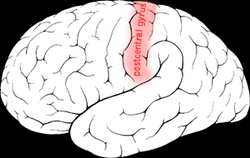

Postcentral gyrus

Postcentral gyrus of the human brain | |

The lateral postcentral gyrus is a prominent structure in the parietal lobe of the human brain. It is the location of the primary somatosensory cortex, the main sensory receptive area for the sense of touch. Like other sensory areas, there is a map of sensory space in this location, called the sensory homunculus.

The lateral postcentral gyrus is bounded by:

- medial longitudinal fissure medially (to the middle)

- central sulcus rostrally (in front)

- postcentral sulcus caudally (in back)

- lateral sulcus inferiorly (underneath)